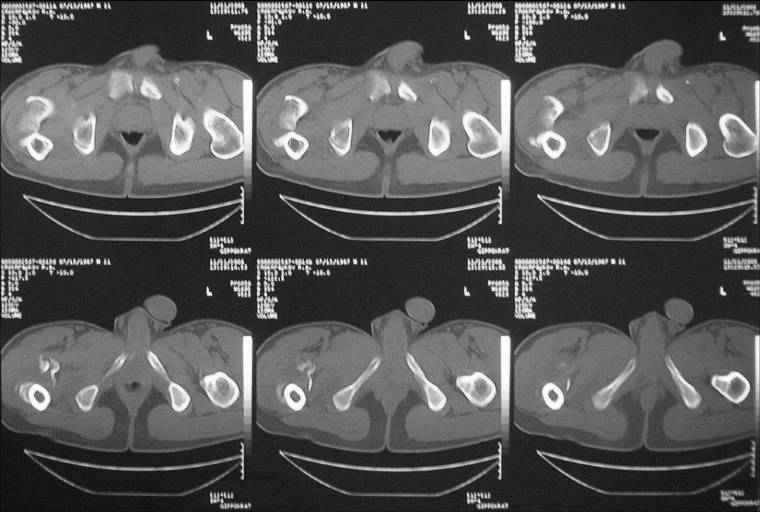

Уважаемые коллеги! Нужен совет. Больной Х., 21 год, ДЗ: ложный сустав вертельной области

правого бедра. Травма 8 мес. назад, ДТП, получил закрытый межвертельный перелом правого

бедра. Лечился в городской больнице одного из городов-спутников г. Караганды скелетным

вытяжением в течение 3 недель, затем кокситной гипсовой повязкой 2 мес.

В настоящее время имеется укорочение конечности на 7 см, умеренная

боль в вертельной области; ходит без костылей, полностью нагружая

больную конечность, при нагрузке отмечается смещение дистального

отломка проксимально примерно на 1,0 см.; объем движений в коленном

суставе сохранен; при пальпации отломков боли нет, умеренная

патологическая подвижность.